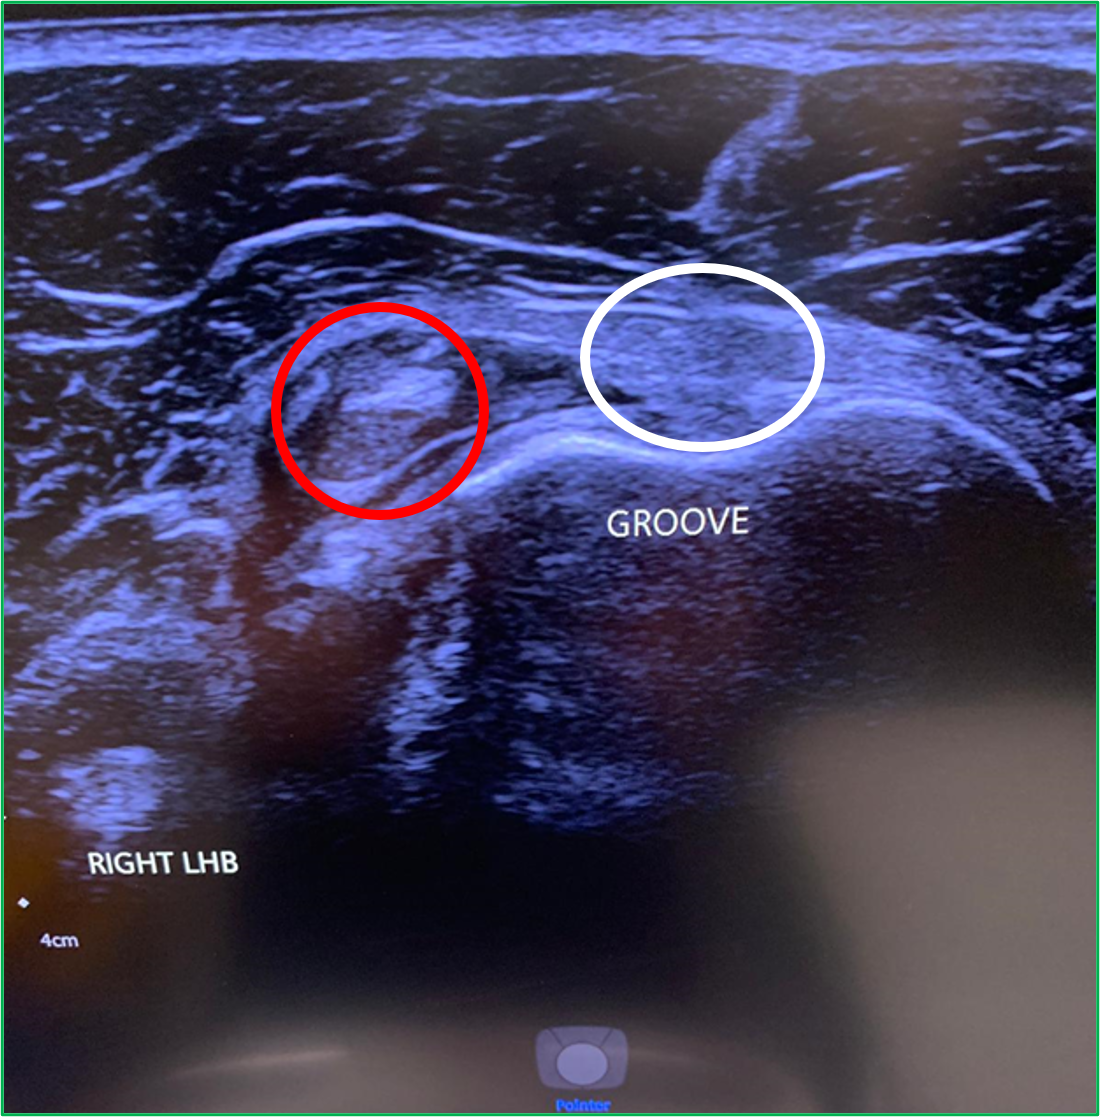

LHB subluxation can happen with contact sports, weight lifting and bodybuilding.

Sometimes the biceps tendon can pop out of its groove. This usually happens because of a tear of the overlying ligament. In other cases, some people are just born with a particularly shallow bicipital groove which puts the tendon at risk of subluxing under load.

Ultrasound findings are of a tendon that is not correctly sited in the bicipital groove (Red circle. The white circle shows where the LHB should sit). To find out more about LHB subluxation: